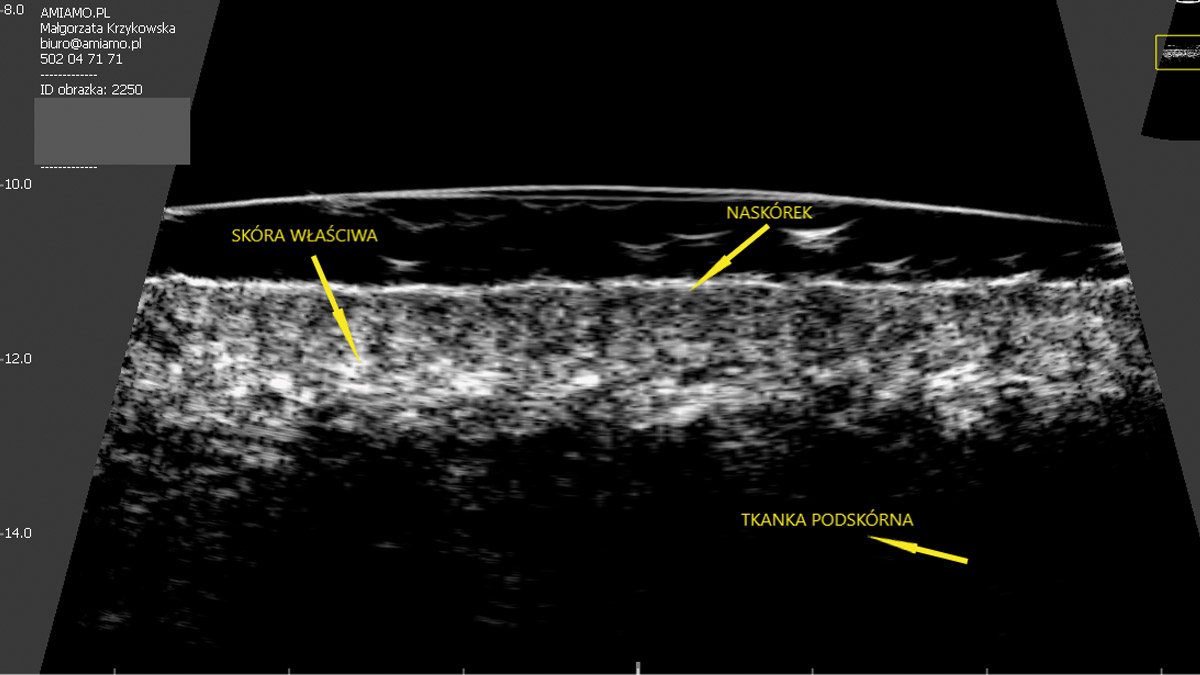

W ostatnich latach do gabinetów kosmetologów wkroczyła najnowocześniejsza i jednocześnie najbardziej zaawansowana metoda diagnostyczna skóry-ultrasonografia. Obrazowanie ultrasonograficzne pozwala zobaczyć skórę od środka. Ma zatem takie „moce”, których nie ma żadna z dotychczas stosowanych kosmetologicznych technik diagnozowania. Czy jest to idealna metoda oceny skóry i czy sprawdzi się w pracy każdego kosmetologa?